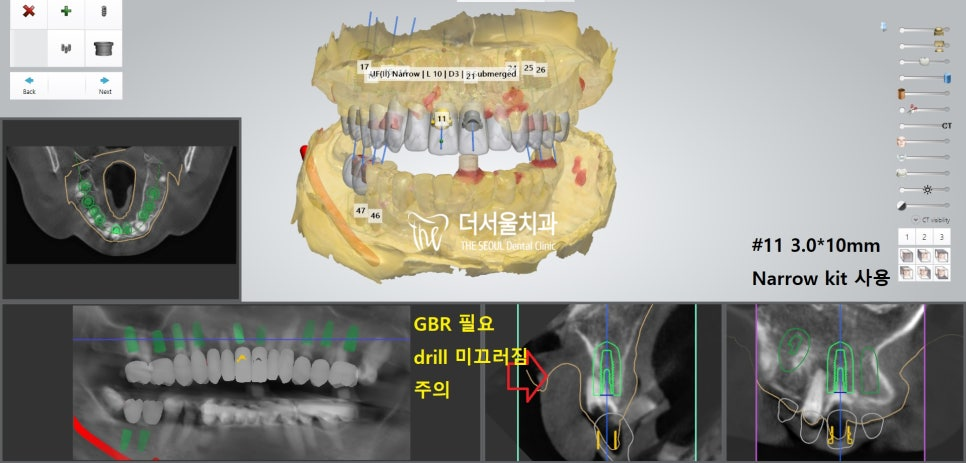

더서울에서 항상 했던 그대로

디지털 분석을 통해 인접치,

주변 조직과의 위치 관계를 파악했습니다.

계산된 위치에 맞춰 픽스쳐를 심어드렸습니다.

개수가 많기 때문에 걱정이 되었지만,

미리 제작된 가이드를 사용하여 수술을 진행하였더니

즉시식립 임플란트 과정을

정확하고 안전하게 끝마칠 수 있었습니다.